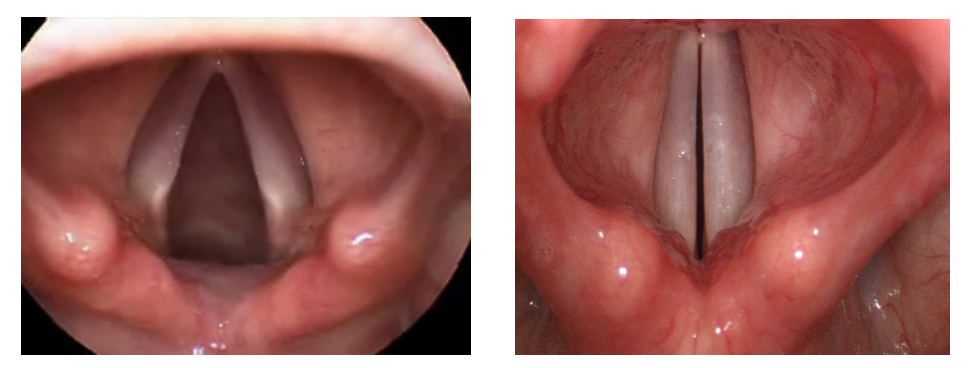

Когда этот воздух выбрасывается, он проходит через наши голосовые связки (голосовые связки), активируетповерхностный слой (покровный слой) этой ткани и передает воздух в резонаторную систему в виде воздушных потоков в обычном частотном диапазоне, создавая волну. Подвижные и неподвижные конструкции в нашей резонаторной системе формируют это движение воздуха и позволяют ему распространяться в окружающую среду в виде человеческих звуков. Голосовые связки – это две структуры в верхней части дыхательного горла, справа и слева. Во время дыхания они отдаляются друг от друга и открывают дыхательные пути; При глотании и издании звуков они сближаются друг к другу. Когда обе голосовые связки приближаются друг к другу и между ними проходит воздух, возникает вибрация, периодически отрезая и открывая воздушный поток. Таким образом генерируется определенная частота звука. Это называется основной частотой. У мужчин основная частота ниже, чем у женщин и детей, поэтому мужской голос более смелый, в среднем 120 Гц. (105-140 Гц.). Базовые значения частоты у женщин и детей высокие. У женщин в среднем 210 Гц. (180-240 Гц.), У детей в среднем 240 Гц в зависимости от возраста и пола.

При обследовании этих пациентов используются объективные методы, такие как видеоингоскопическое исследование, стробоскопическая оценка, аэродинамический и акустический звуковой анализ, выполняемый ЛОРом, оценка восприятия, сделанная ЛОР-врачом, и субъективная оценка, сделанная самим пациентом.